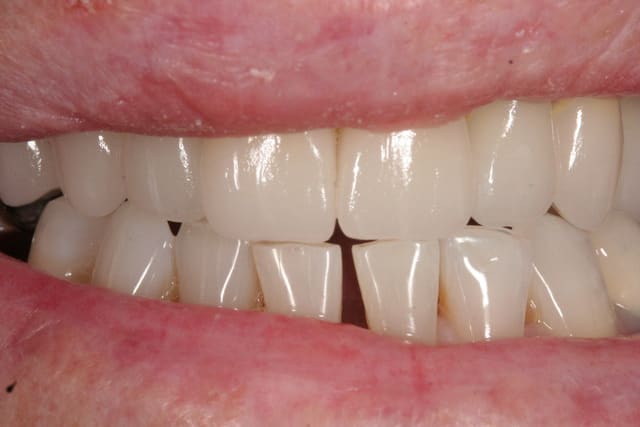

OM1. Yeah !

On passe de la teinte tétracycline la plus sombre à jacob delafont. 8 ans après patient toujours ravi. -)))

J'ai passé tout un après midi à faire ca avec prolongation en soirée et encore aidé du protho ivoclar. Plus jamais. -)

Notez l'effet maquillage encore plus blanc du plus bel effet. -)))